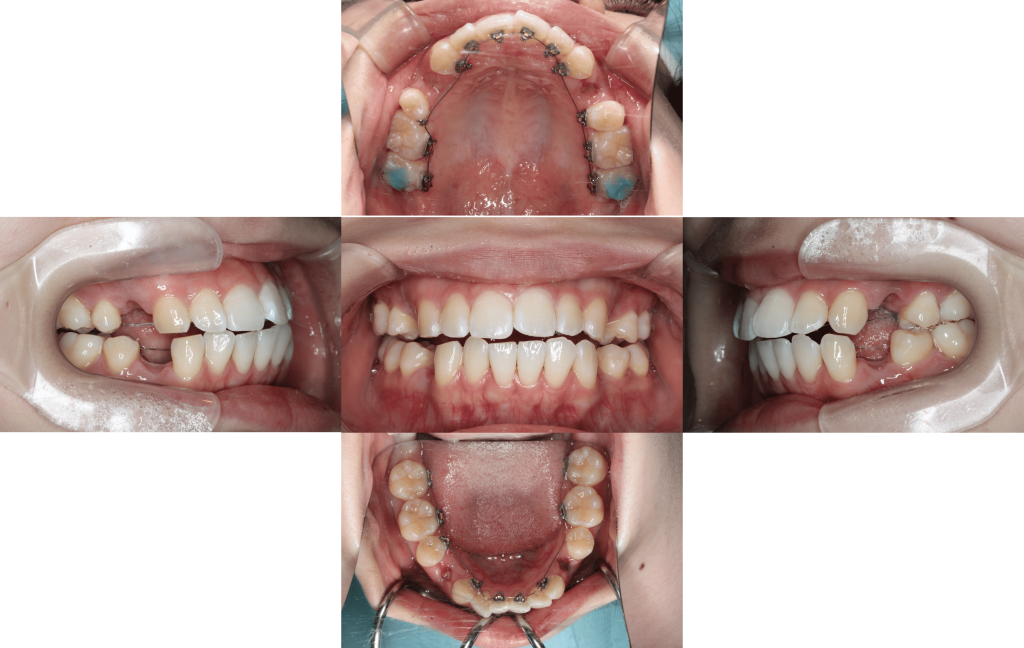

After

約3年経過